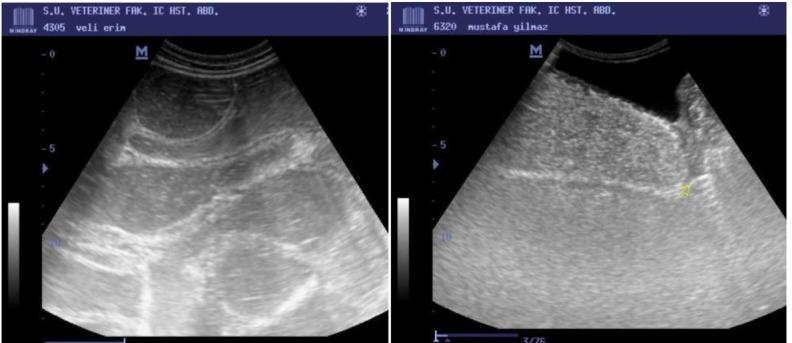

Intestinal obstruction such as atresia coli causes pathophysiological changes in gastrointestinal tissue due to the rise of intra-abdominal pressure. The aim of this study is to determine the intestinal damage with intestinal biomarkers in calves with atresia coli.

The study was conducted on 40 Holstein calves diagnosed with atresia coli with mild to moderate abdominal distention and 10 healthy Holstein calves which served as the control. Blood samples were collected from all calves, and then serum concentrations of intestinal biomarkers were estimated, namely intestinal fatty acid binding protein (IFABP), liver fatty acid binding protein (LFABP), trefoil factor 3 (TFF3), and intestinal alkaline phosphatase (IAP), using commercially available specific bovine ELISA kits. An automatic blood gas analyser was employed for determining the lactate concentration.

The concentrations of serum LFABP (P < 0.01), IFABP, TFF3, IAP, and blood lactate (P < 0.001) were significantly higher in calves with atresia coli than in healthy calves.

The calves affected with atresia coli exhibited severe intestinal damage, and IFABP, LFABP, and TFF3 have significant diagnostic importance and play a useful role in determining the intestinal damage due to intestinal obstruction. High levels of IAP and lactate may serve as a signal for the development of intestinal injury.